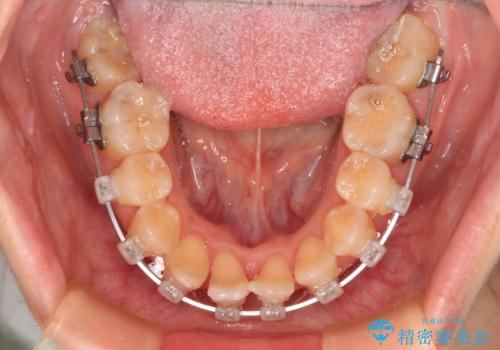

- クリアブラケット

- 治療期間

- 1年

詰め物で隠していた下顎前歯の隙間は、歯軸を改善することで詰め物を除去しても隙間が目立たなくなりました。

まだ改善したいところはありましたが、患者様自身は大変満足されたとのことで、治療を終えることとなりました。